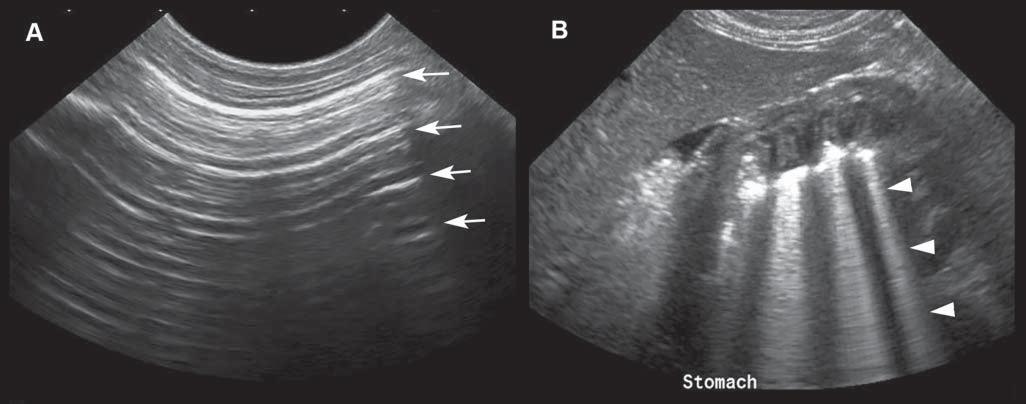

Reverberation

Reverberationartifactstypicallyappearasaseries ofmultiple,equallyspacedlines(Figure1.16A). Theyoccurwhenthebeamhitsahighlyreflective

interface–suchasanairpocket–andsendsitbackas anechoofsimilarintensity.Thehigh-intensityechois partlycapturedbytheprobe,producingahyperechoic lineatthepocket’sinterface,butwithnoechocoming fromdeepertissue.Thesurfaceoftheprobewillreflect thishigh-intensityechoandsenditbackandforth. Aspartoftheechoisperceivedeachtimeitreturns, thecomputercalculatesthetimethathaspassedsince theinitiallaunchofthewavepulseandthusrecords

severalequidistanthyperechogeniclines.Thereis decreasingechogenicityoftheinterfaceasitgoes deeper,duetoagraduallossofwaveintensitythat reboundsandisattenuatedduringitstrajectory.

Comettail isatypeofreverberationartifact–it appearsasaseriesofshortandverycloselyspacedsuccessiveechoes(Figure1.16B)thattypicallydecreasein intensityandwidthindepth.Whengasbubblesform thinlayersseparatedbyliquid–asinthedigestive tract–thewavesreboundbetweenthelayers,resulting inmanyechoesthatreturntotheprobeatregularintervals,makingatrailofechoesintheformofashadow resemblingacomet’stail.Thisartifactisalsoencounteredwithmetallicpelletsorsurgicalclips. Ringdown artifact similarlyappearsasaseriesofparallelreflectivelinesthattypicallyextendbehindagascollection. Ithappenswhenairbubblesresonateattheultrasound frequencyandthenemitreflections.Thiscanbeseen associatedwithirregularlungsurfaces,gastrointestinaltract,andabscesses.Practically,comettailandring downartifactsappearverysimilaronthescreen,even thoughtheyresultfromdifferentphysicalinteractions.